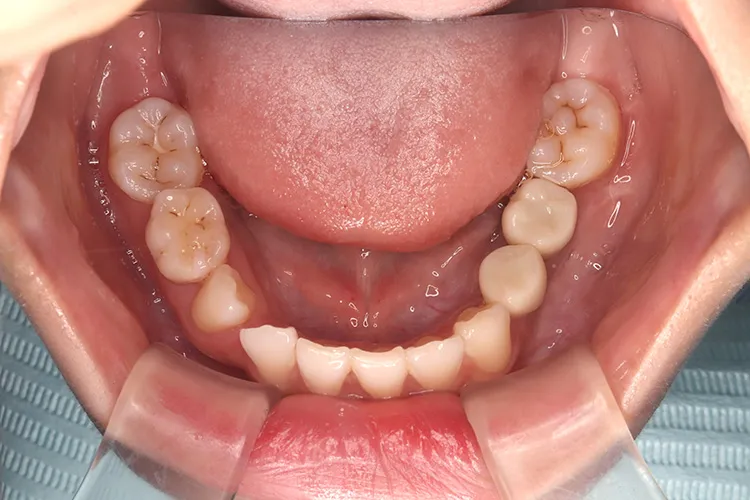

症例9/

永久歯先天欠如

- 治療期間

- 3ヶ月

- 費用

- 147万円(税込)

治療前

治療後

レントゲン画像

治療内容

20歳の患者様の永久歯先天欠如のケースです。右上4・右下5・左下45の他、第二大臼歯も3本先天欠如していました。年齢も若いため、歯を傷める可能性の高いブリッジは選択されず、長期間安定して機能するインプラントを選択されました。このように若年者で永久歯が先天欠如しているケースにも応用できます。